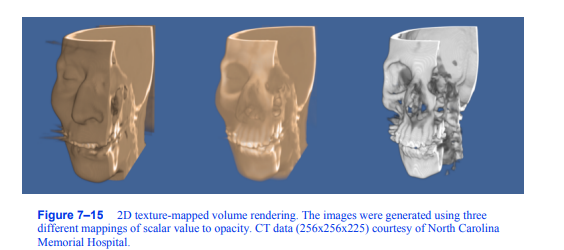

纹理映射体渲染器通过投影一组跨越整个卷的纹理映射多边形来对卷进行采样和混合以生成图像。在2D纹理映射体绘制中,数据集被分解为一组正交切片,沿着与观看方向最平行的体的轴。基本的渲染算法包括以前后顺序在正交切片上进行循环,其中对于每个切片,一个2D纹理被下载到纹理内存中。每个切片都是一个矩形多边形,投影显示整个2D纹理。如果相邻的切片相对于图像大小相差很远,那么可能需要使用软件双线性插值方法从体积中提取额外的切片,以实现一个

图7-15二维纹理映射体绘制。这些图像是使用三种不同的标量值到不透明度的映射生成的。CT数据(256x256x225)由北卡罗来纳州提供

纪念医院。

期望的图像精度。图7 - 14左侧的图像说明了使用2D纹理映射方法渲染的正交切片。使用2D纹理映射体绘制生成的几个示例图像如图7 - 15所示。